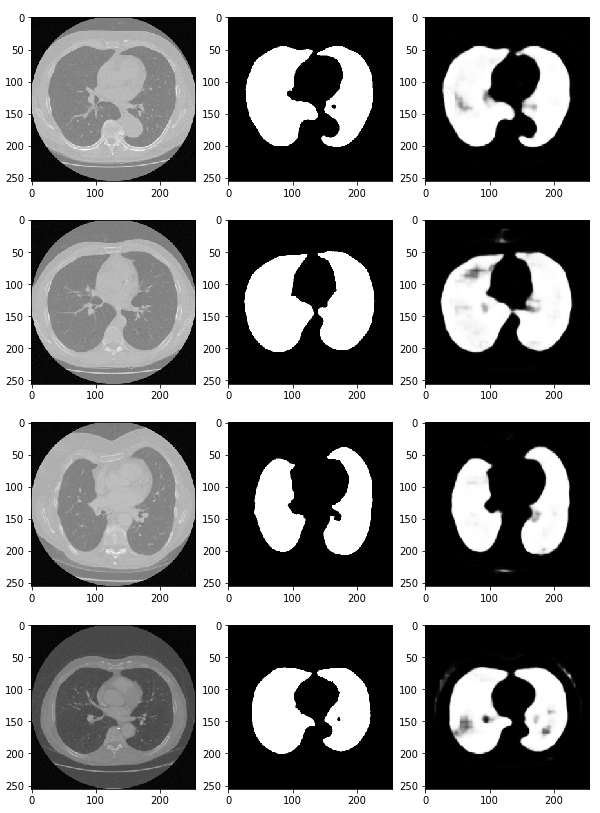

preds = model.predict(x_val) # predict 함수를 통해 (x_val) 검증한다

fig, ax = plt.subplots(len(x_val), 3, figsize=(10, 100))

for i, pred in enumerate(preds):

ax[i, 0].imshow(x_val[i].squeeze(), cmap='gray') # 첫 번째 열에는 CT 데이터(x_val[i])를 삽입

ax[i, 1].imshow(y_val[i].squeeze(), cmap='gray') # 두 번째 열에는 정답 데이터를 넣는다.

ax[i, 2].imshow(pred.squeeze(), cmap='gray') # 세 번째 열에는 우리가 예측한 결과값을 그려본다.

# 이러한 딥러닝을 활용하여 산소의 수치, 적혈구, 백혈구의 농도 등 수치적 데이터를 가지고 예측하는 방법도 존재함.